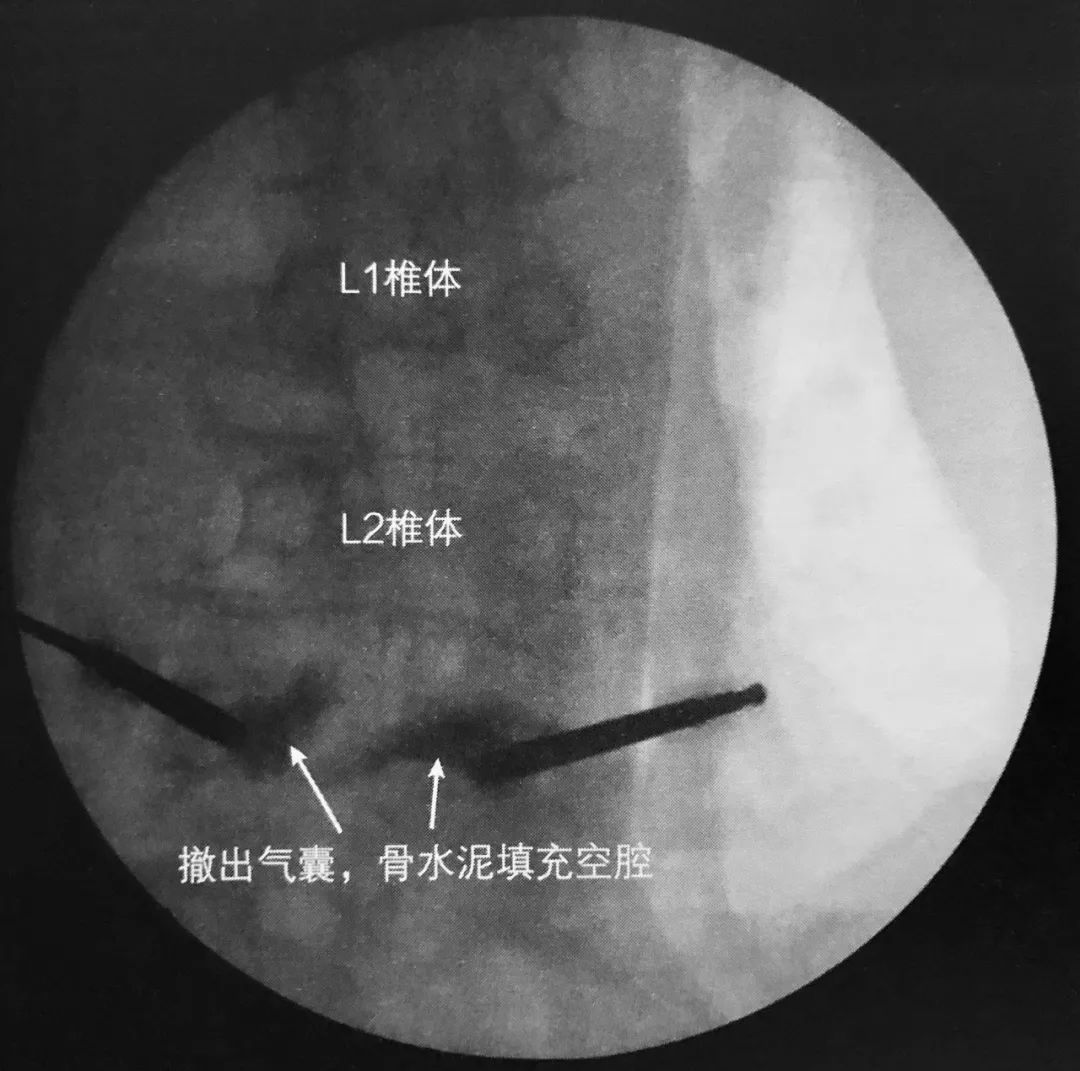

7. 透视下向椎体内注入骨水泥,在正侧位片上仔细观察以确保椎体边缘不被侵犯。如果发现骨水泥溢出,则停止注入。应避免将骨水泥注入椎体后部。

8. 理想情况下,正位片上骨水泥充填应该通过中线。